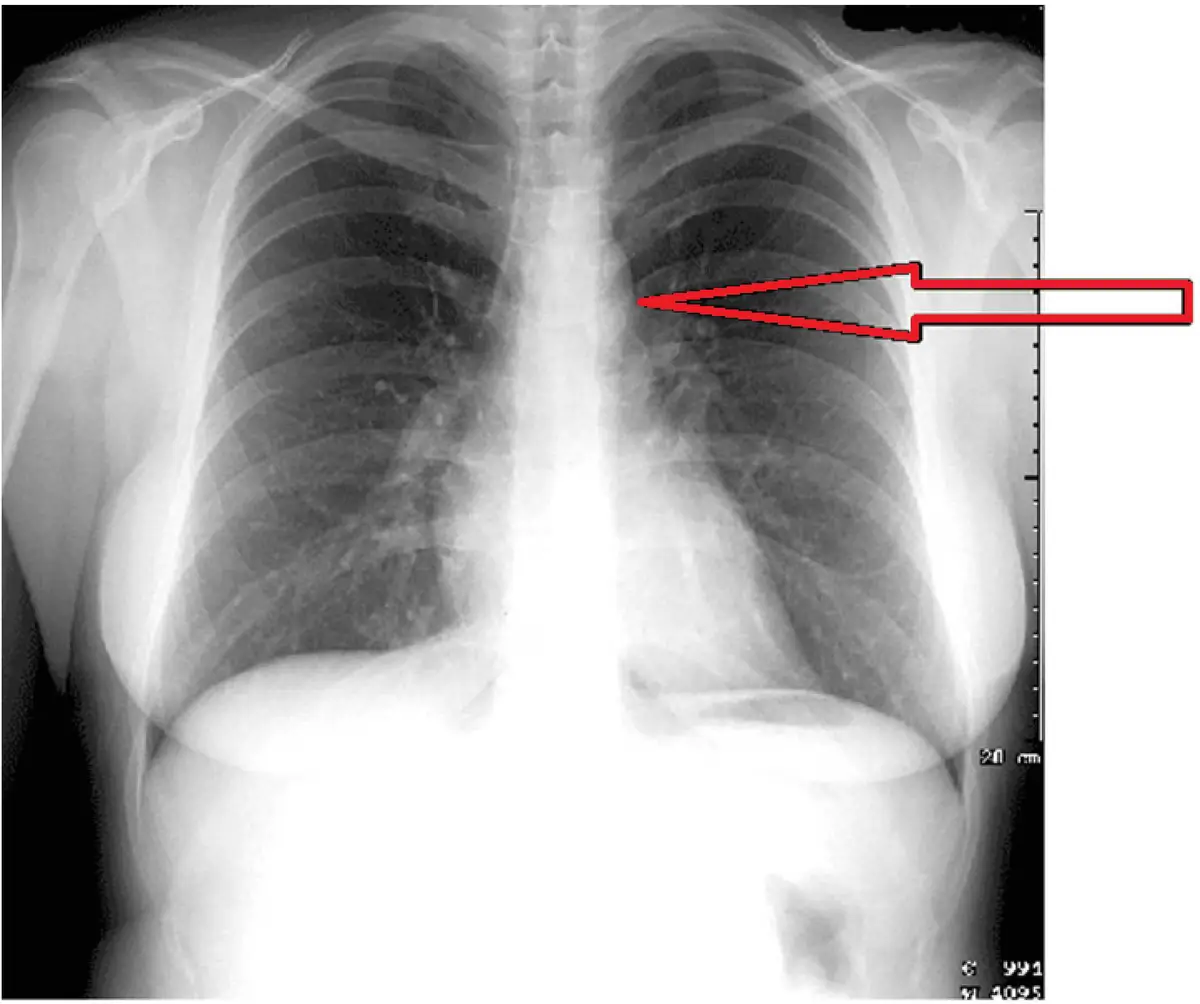

本題提供一張標準後前位(PA view)胸部X光,為成人胸廓正面影像,整體肺野清晰,縱膈腔結構可辨。圖中有一個明顯的紅色箭頭,從圖片右側(病人左側)指向縱膈腔左側上方的特定結構。

箭頭指向位置分析:

- 箭頭指向左側縱膈腔的上方突出輪廓,位於心臟陰影上方、左主支氣管開口上方的高度。

- 此結構呈圓弧形突出(knob/knuckle 外觀),形成左側縱膈腔最上方的凸起輪廓。

- 依位置判斷,此結構位於 T3–T4 椎體水平,介於升主動脈弓(上方)與左肺動脈(下方)之間。

- 箭頭指向的正是此明顯的圓形結節狀突起,即主動脈結(aortic knob),又稱主動脈結節(aortic knuckle)。

周圍結構對照:

- 主動脈結下方(稍後方)的凹陷即為主動脈-肺動脈窗(aortopulmonary window)。

- 再往下方才是左肺動脈(left pulmonary artery)的輪廓。